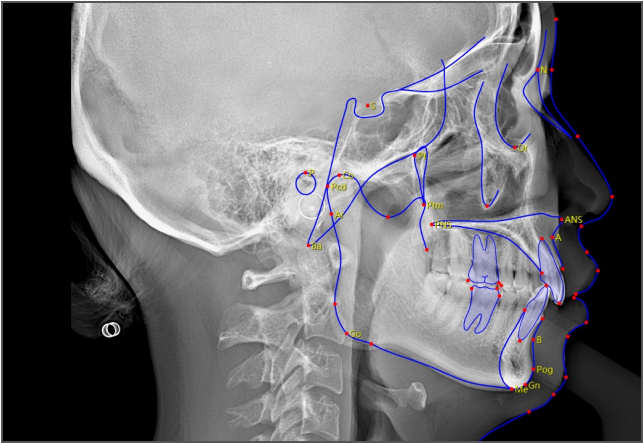

• lamtau AI头影测量

AI头影测量

单侧头影测量 专利 首创

偏颌患者的侧位片左右侧的影像不对称,实际正畸测量时会产生较大的误差。有方医疗推出单侧头影测量功能。这一功能有效解决了这一临床问题,在口腔正畸领域广受好评,并于2023年成功获得国家发明专利授权。

单侧头影测量